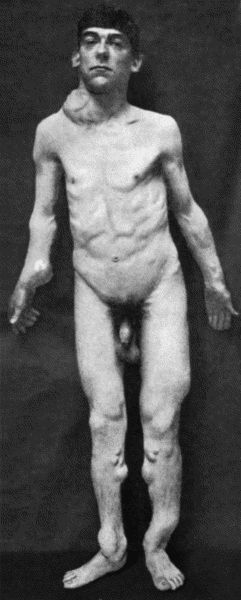

Another modification is to raise the flap but leave it connected at both ends like the piers of a bridge; this method is well suited to defects of skin on the dorsum of the fingers, hand and forearm, the bridge of skin is raised from the abdominal wall and the hand is passed beneath it and securely fixed in position; after an interval of 14 to 21 days, when the flap is assured of its blood supply, the piers of the bridge are divided (Fig. 1). With undermining it is usually easy to bring the edges of the gap in the abdominal wall together, even in children; the skin flap on the dorsum of the hand appears rather thick and prominent—almost like the pad of a boxing-glove—for some time, but the restoration of function in the capacity to flex the fingers is gratifying in the extreme.

Fig. 1.—Ulcer of back of Hand covered by flap of skin raised from anterior abdominal wall. The lateral edges of the flap are divided after the graft has adhered.